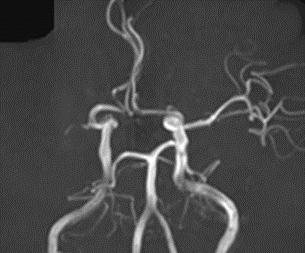

バイパス術で増加した脳血管